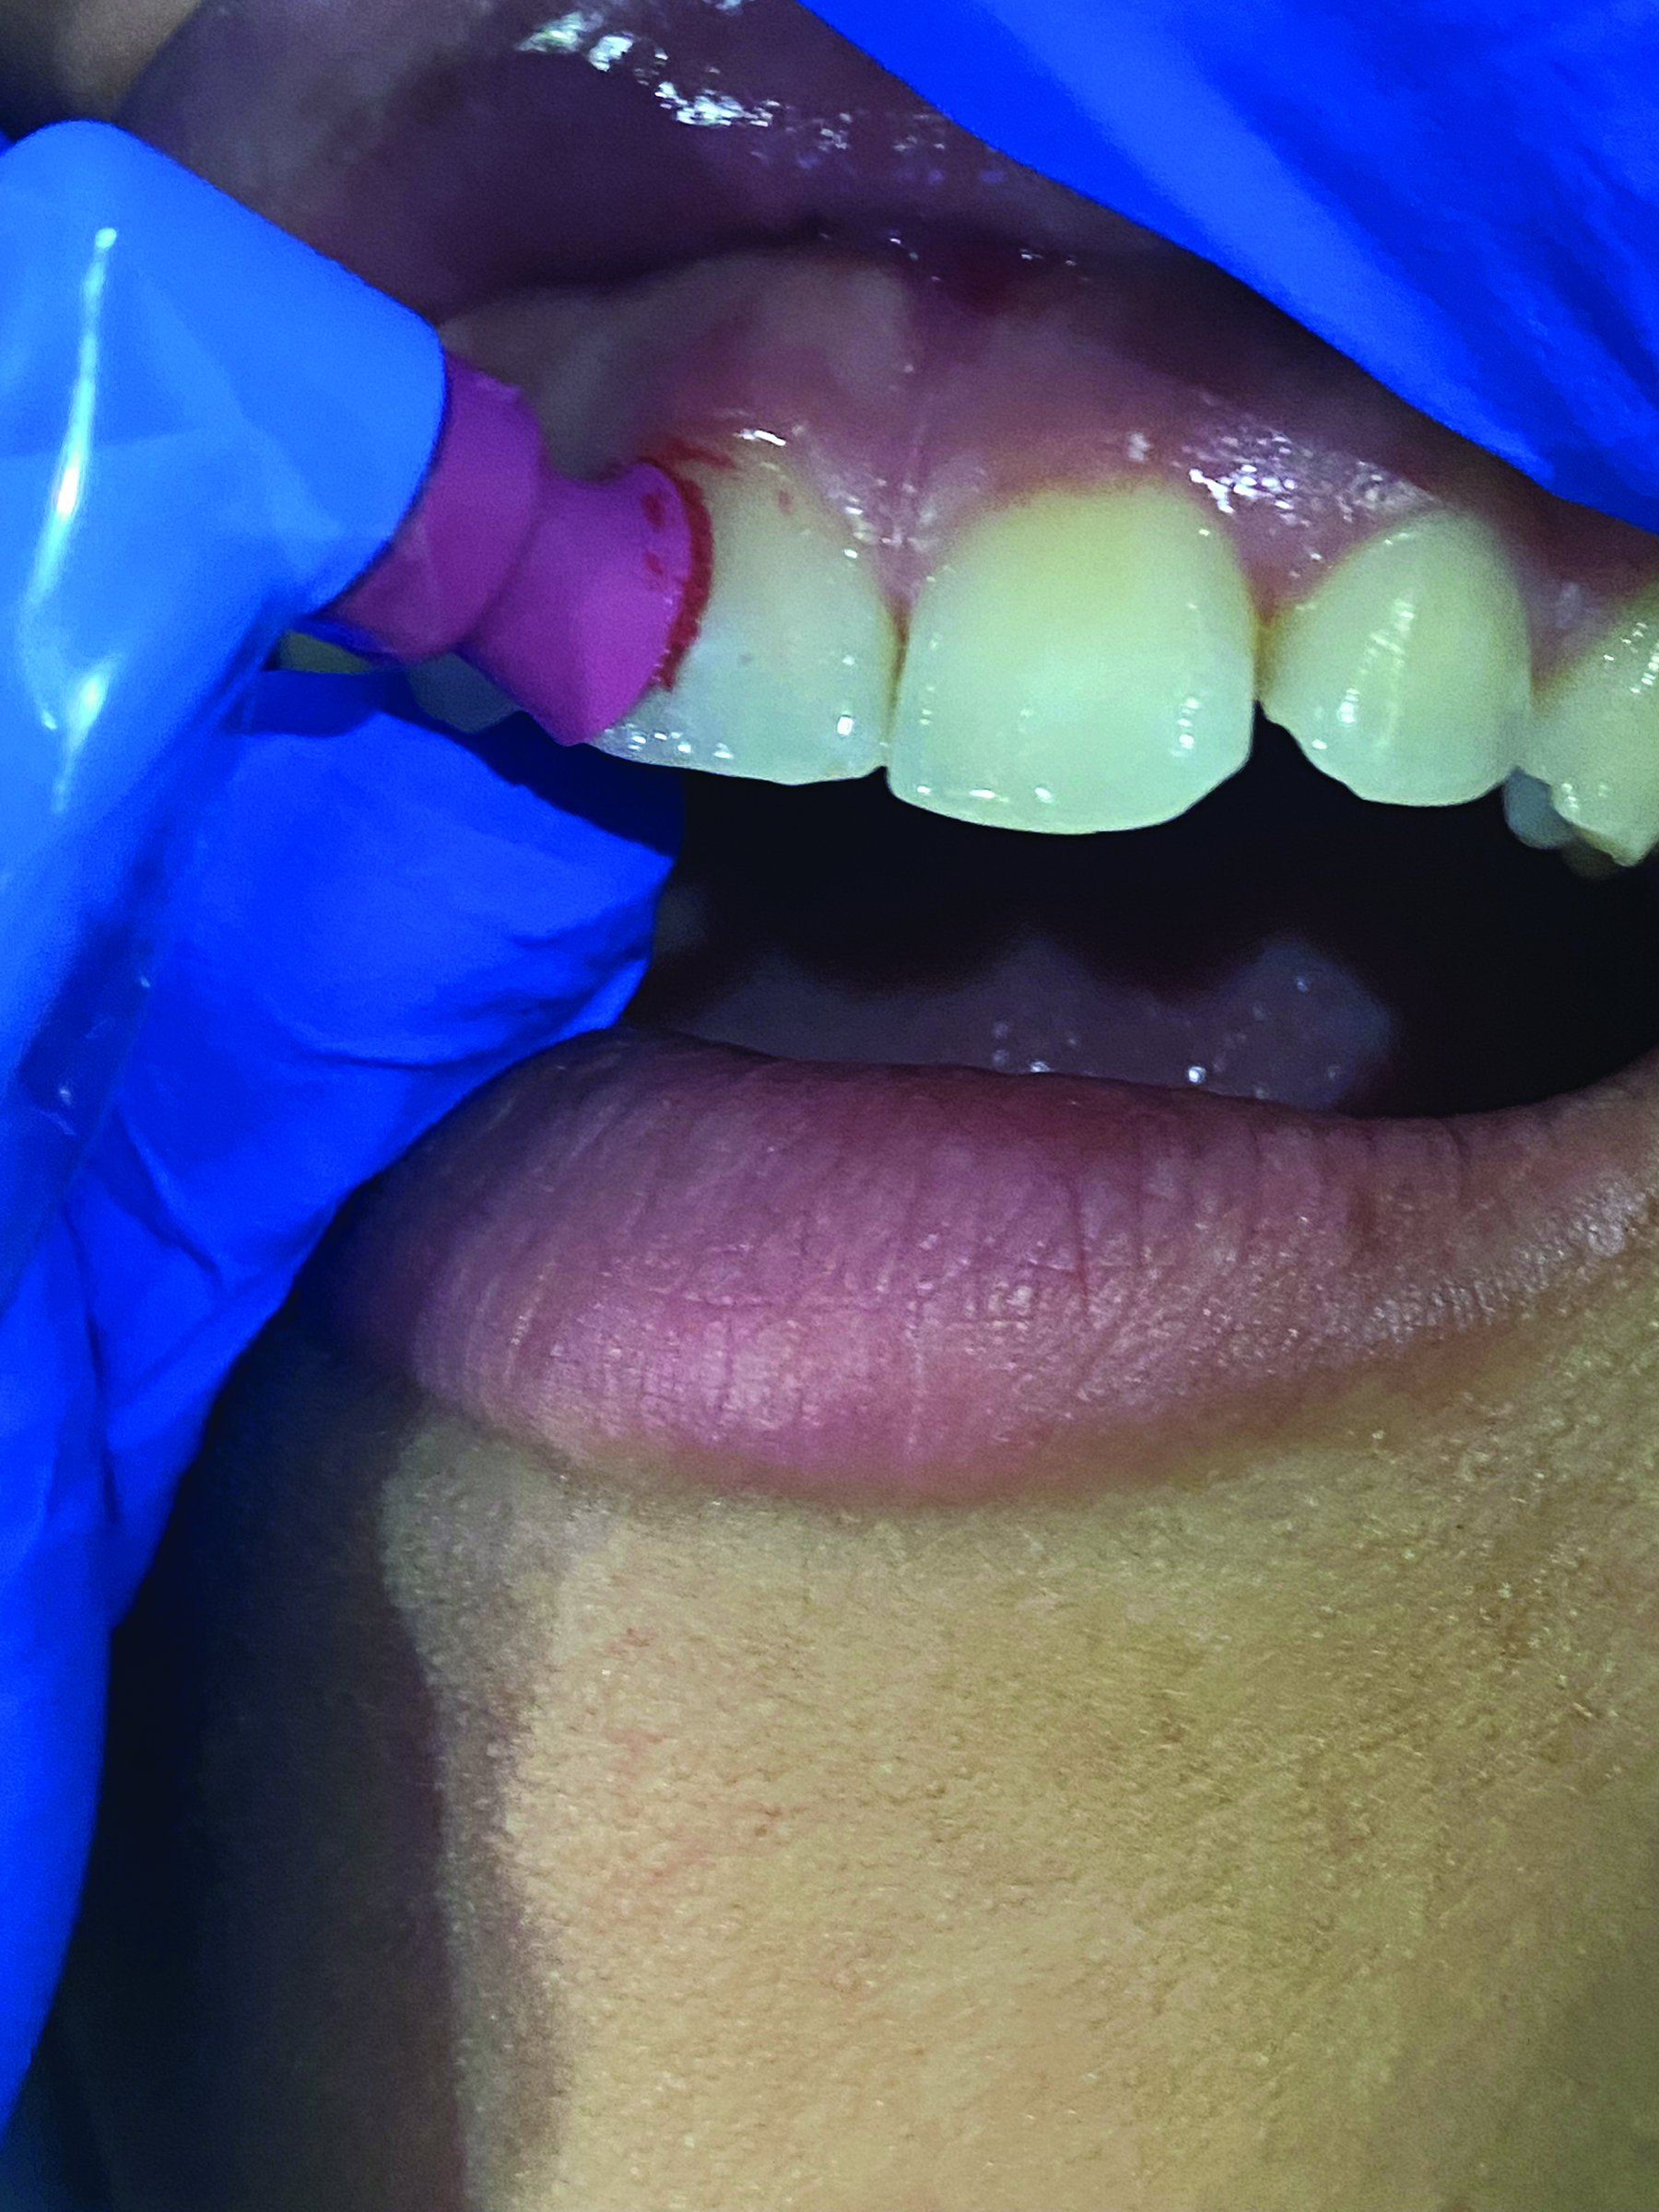

(7.) Fluoride varnish is one of the most common dental products used to help protect vulnerable tooth surfaces.

Figure 7

A thin fluoride-rich layer of enamel is compromised during debridement and polishing procedures. This layer can take upwards of 3 months to regenerate, leaving the tooth susceptible to daily sugar and acid attacks, which can result in a number of dental conditions such as caries and dentinal hypersensitivity. It is prudent for the clinician to treat and protect the compromised surfaces. As a preferred quick and easy in-office treatment, fluoride varnish is one of the most common dental products on the market to help protect vulnerable tooth surfaces until patients return for their next recare visit. Most varnish materials are comprised of a concentrated form of sodium fluoride (NaF) suspended in an alcohol- and resin-based solution with some additional additives, including a film-forming agent, flavors, sweetener such as xylitol (which has therapeutic benefits as well), and additives that aid in remineralization20,21 (Figure 5 through Figure 7). Examples include products such as Colgate® PreviDent® Varnish (Colgate Oral Health), FluoroDose® (Centrix), and ACCLEAN® 5% Sodium Fluoride Varnish (Henry Schein).

Once varnish is applied to the tooth surface, fluoride ions are attracted to the demineralized areas and integrate with hydroxyapatite to begin reforming the fluoride-rich enamel layer on the tooth surface.21 Most varnish products have a solubility profile that permits sustained release of fluoride over a specified period of time, offering teeth even greater protection over a longer duration.